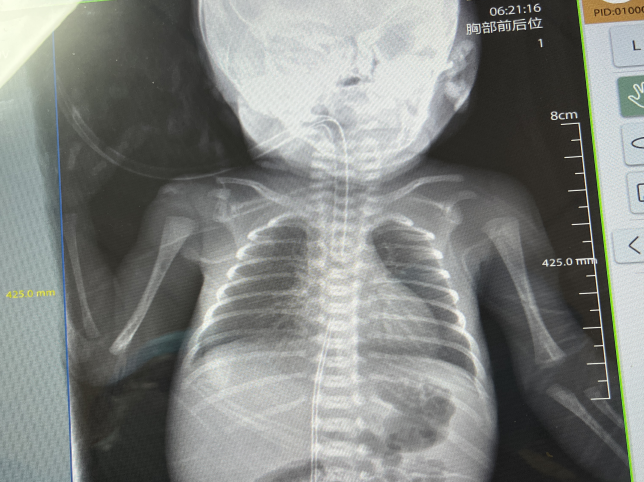

宝宝出生瞬间,产房内急救随即启动。医护人员第一时间完成胸部X线检查,精准评估肺部情况,并迅速通过气管内注入肺表面活性物质,为脆弱的呼吸功能筑起第一道“防护墙”。